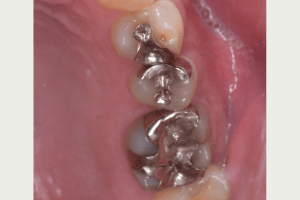

銀歯の中身はどうなってる??

麻布十番の歯医者さんで歯の検診を受けているイメージ

銀歯の中身の写真

麻布十番の歯医者さんで銀歯を外す前の症例写真

麻布十番の歯医者さんで銀歯を外す後の症例写真

こちらは銀歯を外す前と後の写真の比較になります。黒い部分が虫歯になっています。銀歯をつけているとなかなかレントゲンにも虫歯として映ってこないことが多いので、発見が遅れてしまうことがあります。